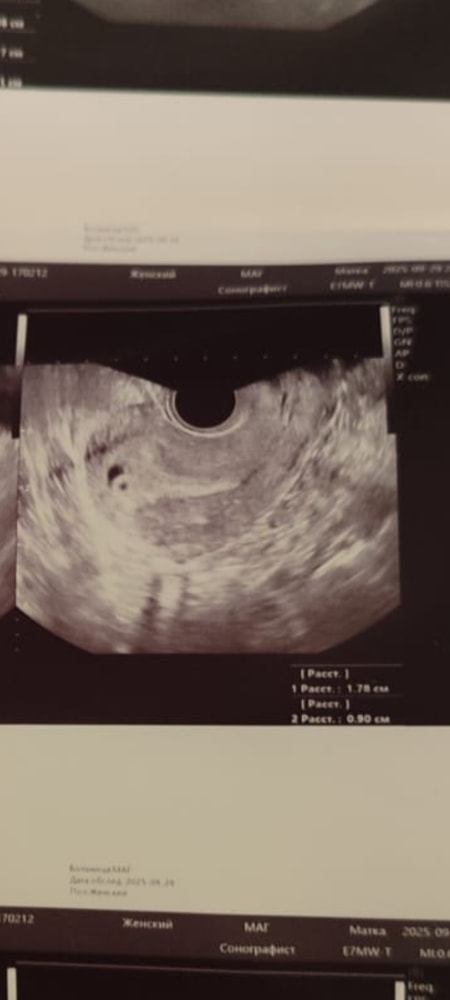

Год пытались зачать, и вот наконец получилось -- на 2 и 5 день задержки сдала хгч, прирост в два раза. Мы обрадовались и стали ждать. На пятой неделе стало тянуть живот. Пошла на УЗИ -- увидели плодное яйцо и ретрохондриальную гематому, довольно крупную. Поставили угрозу. Назначили прогестерон.

Через неделю пришла на УЗИ снова. Акушерский срок 6 недель -- ожидали увидеть эмбрион, но на экране только плодное яйцо. Узистка говорит: похоже, беременность не развивается. А потом приглядывается и находит по соседству ещё одно "пятнышко".

"То ли второе плодное яйцо, то ли скопление жидкости. Пока эмбрионов не видно, точно сказать не могу. Ставлю замершую под вопросом. Через 10 дней посмотрим, станет ясно" -- сказала мне узистка.

УЗИ 5 недель.